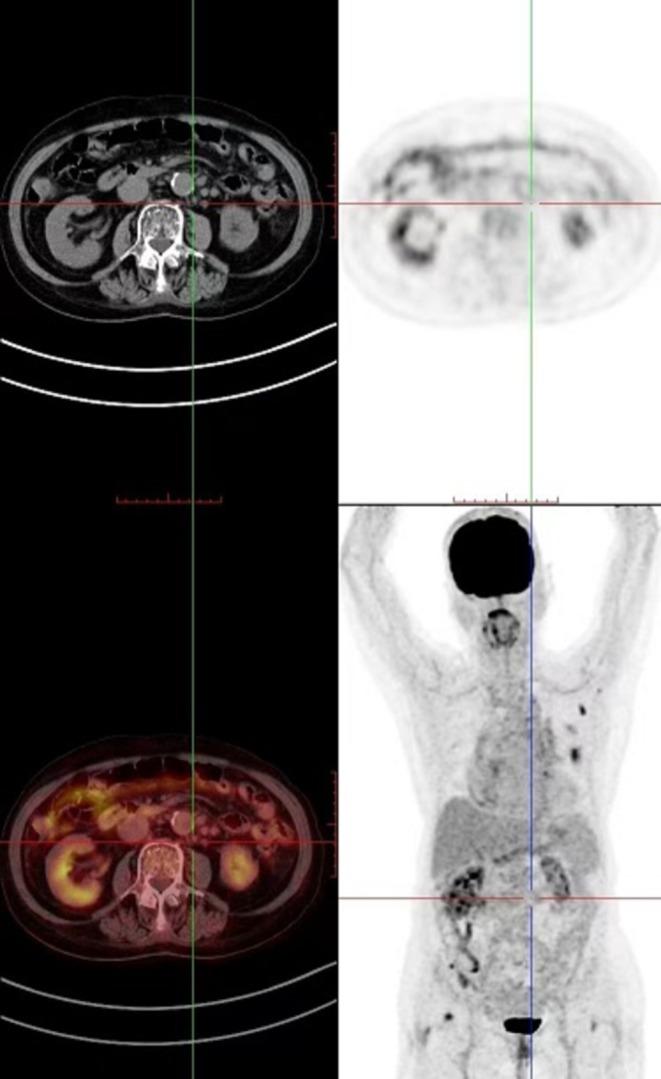

IgG4-Related Disease Mimicking Metastatic Malignancy: Polyserositis and Abdominal Lymphadenopathy.

In patients presenting with multiple space-occupying lesions, preserved general condition, and normal or mildly elevated tumor markers, IgG4-related disease (IgG4-RD) should be considered in the differential diagnosis. We report an extremely unusual case of IgG4-RD mimicking metastatic malignancy, with polyserositis and widespread abdominal lymphadenopathy.